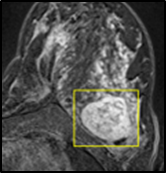

We tested the algorithm by varying the number of markers between and . Fig 2 describes the segmentation results obtained using different numbers of markers. This plot indicates that markers were found to be optimal using this segmentation approach, yielding satisfactory results.

where refers to the ROIs segmented by our algorithm and is tumor area as determined by manual segmentation. Table 1 summarizes the segmentation accuracy achieved using the proposed method for all 106 cases. The average dice coefficient was found to be 0.780.17 and average Jaccard index was 0.670.21. Fig 3 demonstrate four sample segmentation outputs which are overlaid on manual segmentations provided by two radiologists. It can be seen, that the proposed method could accurately segment the lesions with some marginal errors for medium to large tumors. However, for cases comprising disjoint lesions, the method failed to segment all small lesions and in some cases incorrectly labeled healthy tissue as lesions. This is because in some cases there is a high degree of overlap in the intensity distributions of healthy breast tissue and lesions, and the ROI drawn by the radiologist is very large in the case of disjoint lesions, in order to cover the entire area over which multiple lesions are distributed.